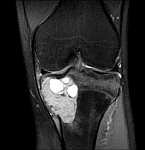

- Resection of benign and malignant tumors of the bone and soft tissue

The presentation of findings, X-ray images and CT or MRI can also be made by the attending physicians by mail or e-mail to the above-mentioned contact persons.